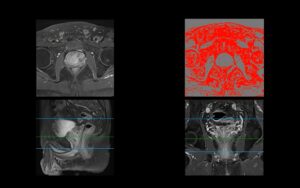

DWI is specifically designed to be sensitive to this restriction. The imaging sequence applies magnetic gradients that cause freely moving water molecules to lose their signal, while water molecules with restricted movement retain their signal. As a result, areas of high cellular density appear “bright” on DWI scans. This makes diffusion-weighted imaging prostate cancer a vital tool, as it provides a functional map of cellularity that complements the anatomical information from other prostate lesion MRI sequences. The unique contrast provided by DWI prostate MRI helps radiologists quickly identify suspicious areas that warrant further investigation.

When a radiologist reviews a prostate MRI, the DWI sequence is a primary indicator of potential trouble. Cancerous lesions typically appear as focal areas of high signal intensity—or bright spots—on the high b-value DWI images. This brightness signifies restricted water diffusion, a hallmark of densely packed cancer cells.

However, a bright spot on DWI alone isn’t enough for a diagnosis. Other conditions, like inflammation, can also restrict water movement. This is where the ADC map becomes essential. A true cancerous lesion will typically be bright on DWI and correspondingly dark on the ADC map. This “bright on DWI, dark on ADC” pattern is a classic sign of a clinically significant lesion. Radiologists analyze these signal intensity patterns to evaluate the likelihood of malignancy and correlate their findings with what is known about the underlying pathology of prostate tumors.

While DWI provides a qualitative visual of restricted diffusion (the bright spots), the Apparent Diffusion Coefficient (ADC) map gives us a quantitative measurement. An ADC map is not a direct scan but is mathematically calculated from a series of DWI images acquired at different gradient strengths, known as b-values. By comparing how the signal from water molecules fades at these different b-values, the software can calculate a specific diffusion value for each pixel in the image.

These values are then compiled into an ADC map, where the brightness of each pixel represents how freely water can move. Low ADC values (appearing dark on the map) indicate highly restricted diffusion, whereas high ADC values (appearing bright) signify unrestricted diffusion. This makes the apparent diffusion coefficient MRI a powerful tool for objectively measuring tissue characteristics, turning a visual observation into hard data. When evaluating ADC prostate cancer findings, these quantitative values provide a more objective measure of a lesion’s cellularity.